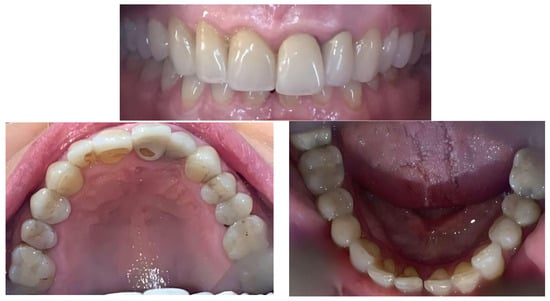

A 65-year-old female patient consulted an orthodontist about the possibility of changing the position of the left upper central incisor, which was in a vestibular position in relation to the rest of the teeth. Initial photos of the patient are presented in Figure 1. Tooth 21 was endodontically treated for pulpitis after a childhood injury. Due to the weakening of the tooth’s hard tissues and the aesthetic issue, the crown of the tooth was many times sealed with different adhesive materials that no longer fulfil their function. In 2010, a crown was made of zirconium oxide, but according to the patient, it was not properly modelled on the palatal surface. Damage to the palatal surface of the crown cemented in the patient’s mouth indicated attempts to improve occlusal contacts by grinding porcelain. Examination of the occlusal contacts in maximal intercuspation showed the presence of dominant contacts on the posterior teeth and teeth 31, 32 and 21 (Figure 2).

Figure 1.

Initial photos of the patient.